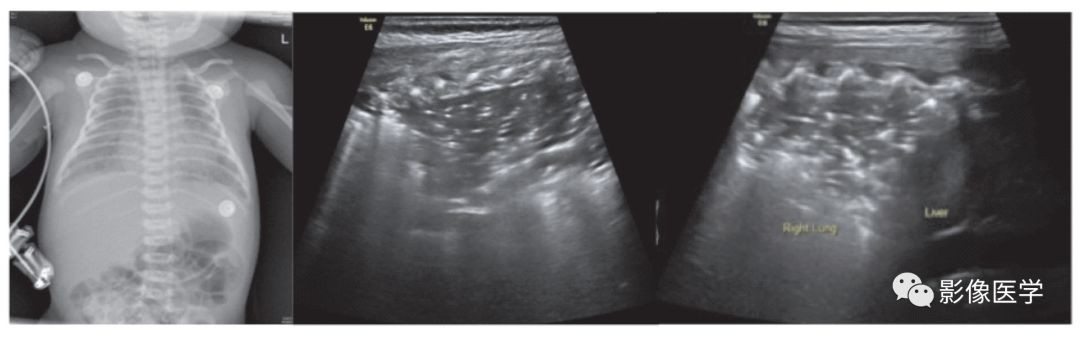

图 6-2 重症感染性肺炎(1)

胎龄38+2周,剖宫产分娩,出生体重3 420g。因呼吸困难3d于出生后20d入院。体温38℃,双肺可闻及密集细湿啰音。血常规:WBC 22×109/L,N 78%,单核细胞比例12.2%,CRP 66.8mg/L。胸部X线检查结果符合新生儿肺炎改变。肺脏超声显示双肺边缘不规则的大面积实变区伴支气管充气征,胸膜线模糊或消失,A线消失。

图6-3 重症感染性肺炎(2)

胎龄32+6周,出生体重2 400g。出生后7d,呼吸困难,胸部X线检查结果符合新生儿肺炎改变。肺脏超声显示双肺大面积肺实变伴支气管充气征,实变区边缘不规则,胸膜线模糊或消失,A线消失。